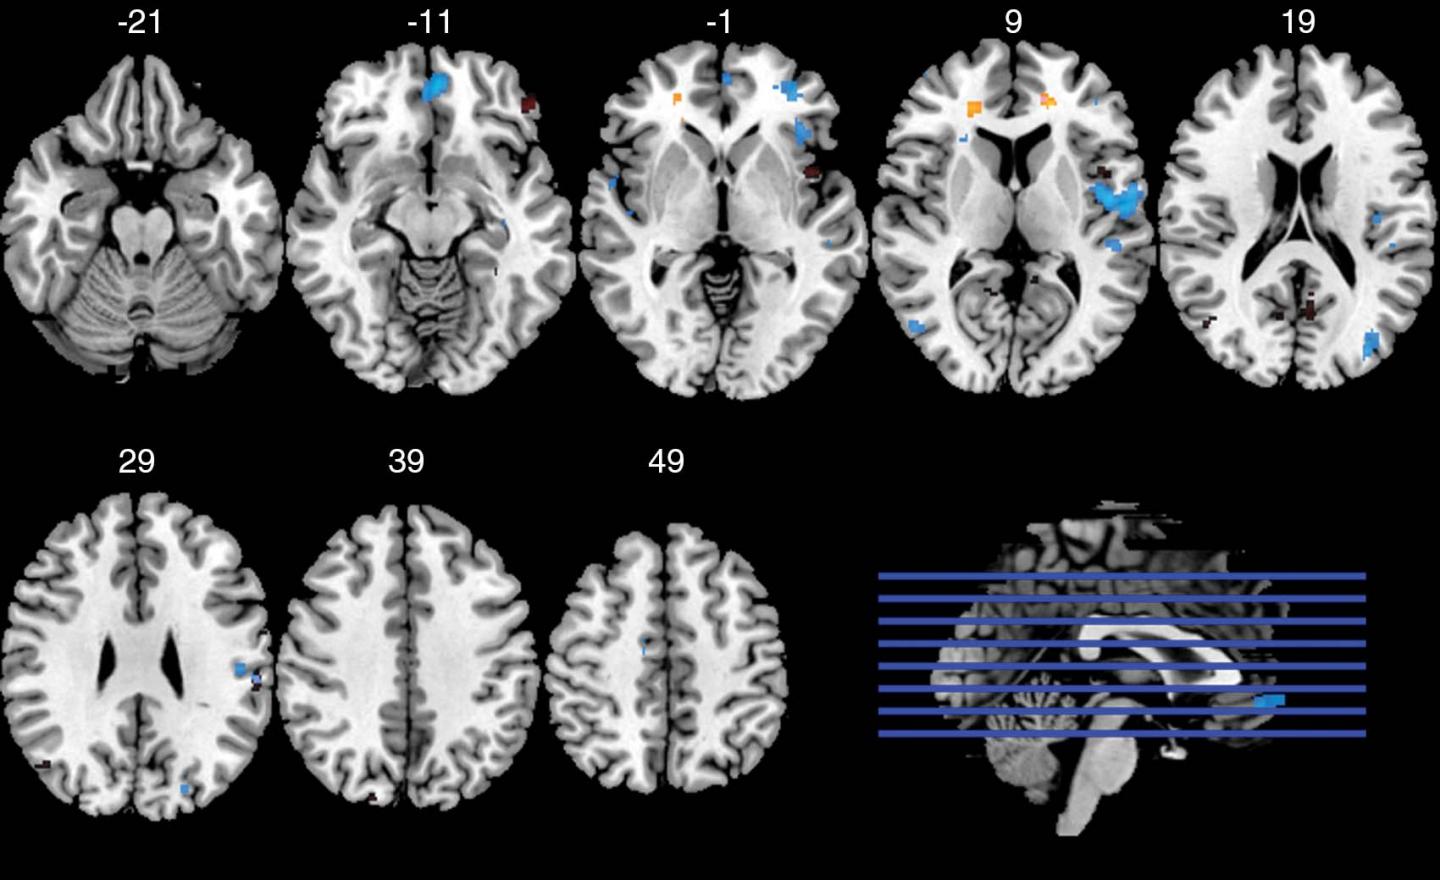

Two MRI techniques -- diffusion tensor imaging (DTI) and functional MRI (fMRI)--were used to examine 61 of the former players. MRI data from the other three players were excluded due to excessive movement or inability to complete the MRI exam. DTI was used to analyze white matter structural integrity, while fMRI was used to assess brain function while the players performed a memory task.

"While DTI and fMRI have been used previously in the field of concussion research, we are among the first to combine the two techniques," said co-author Michael Clark, medical student at UNC-Chapel Hill. "We were interested in how white matter and the ability to recruit brain resources to complete a memory task might be affected by head impact exposure in terms of career length and the position played. By using two different and complementary types of MRI, we were able to see the relationship between structure and function, both of which are affected by head impact exposure."

The non-speed players with a history of recurrent concussion had reduced integrity in the frontal white matter and lower measure of activation during the fMRI task than those with one concussion or less. This was not the case for the speed players.

The interactions observed between concussion histories and playing positions suggest there may be important differences in the mechanisms of injury between speed and non-speed players. The magnitude, location and frequency of head impacts in football differ by position. Offensive backs experience impacts at greater acceleration. Linemen, however, tend to experience a greater overall frequency of impacts, and have the greatest proportion of impacts to the front of the helmet. The high proportion of frontal impacts experienced by non-speed players may result in more localized damage to frontal white matter tracts as compared to the more variable impact locations experienced by speed position players.